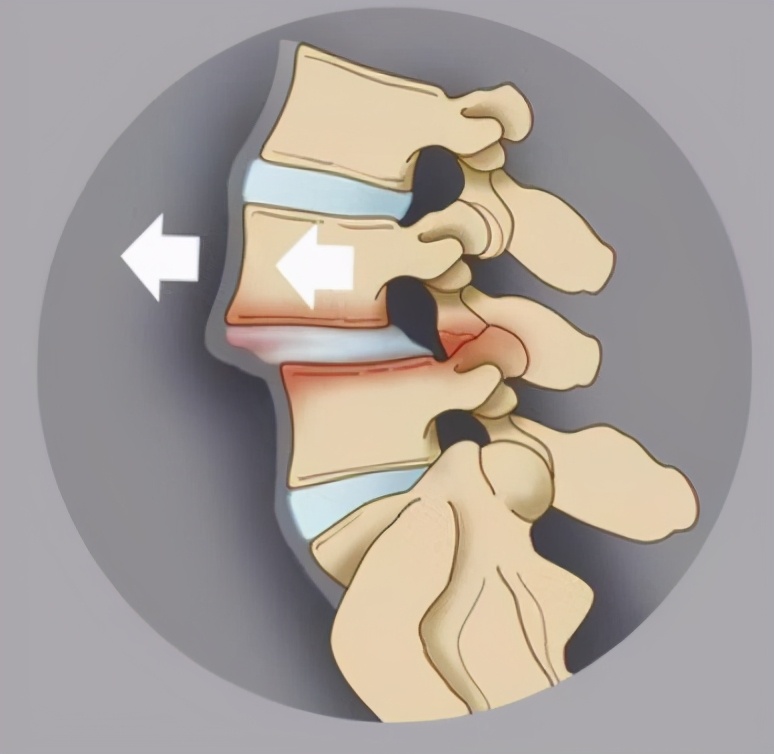

正常人的腰椎后缘是一条连续的曲线。如果这条曲线不连续了,则意味着其中一个腰椎的椎体相对于邻近的下一个腰椎向前(较多)或向后(较少)滑移,就称为腰椎滑脱。

腰椎滑脱是由于先天性发育不良、创伤、劳损等原因造成上位椎体与下位椎体位置错位,多见于20~50岁,男性多于女性,常见部位是腰4或腰5。